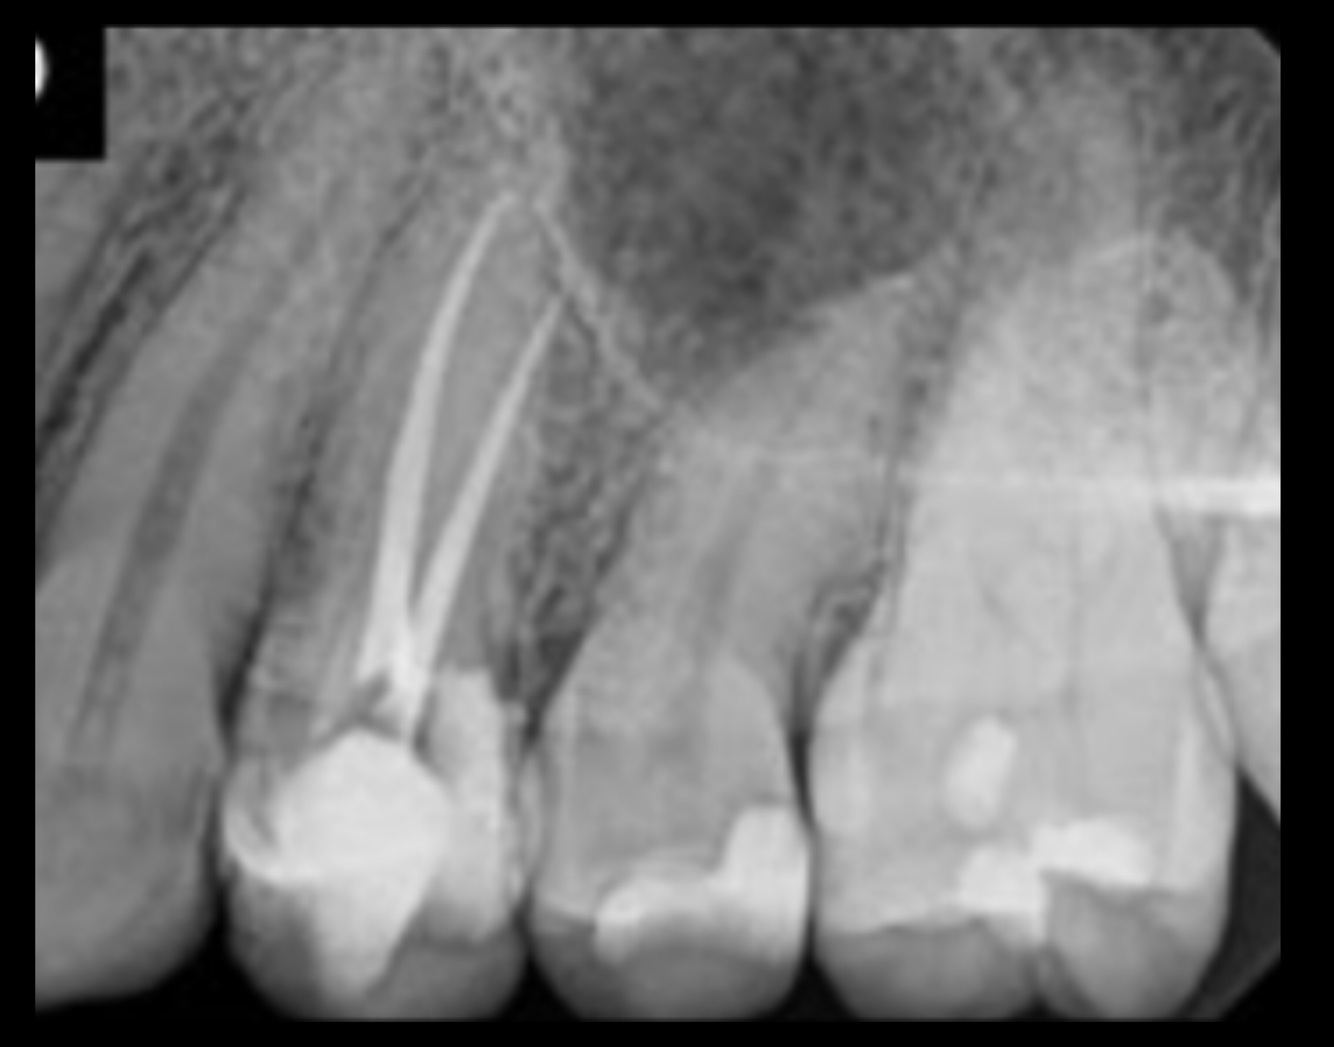

4

Q

The RCT done on:

13

14

17

A